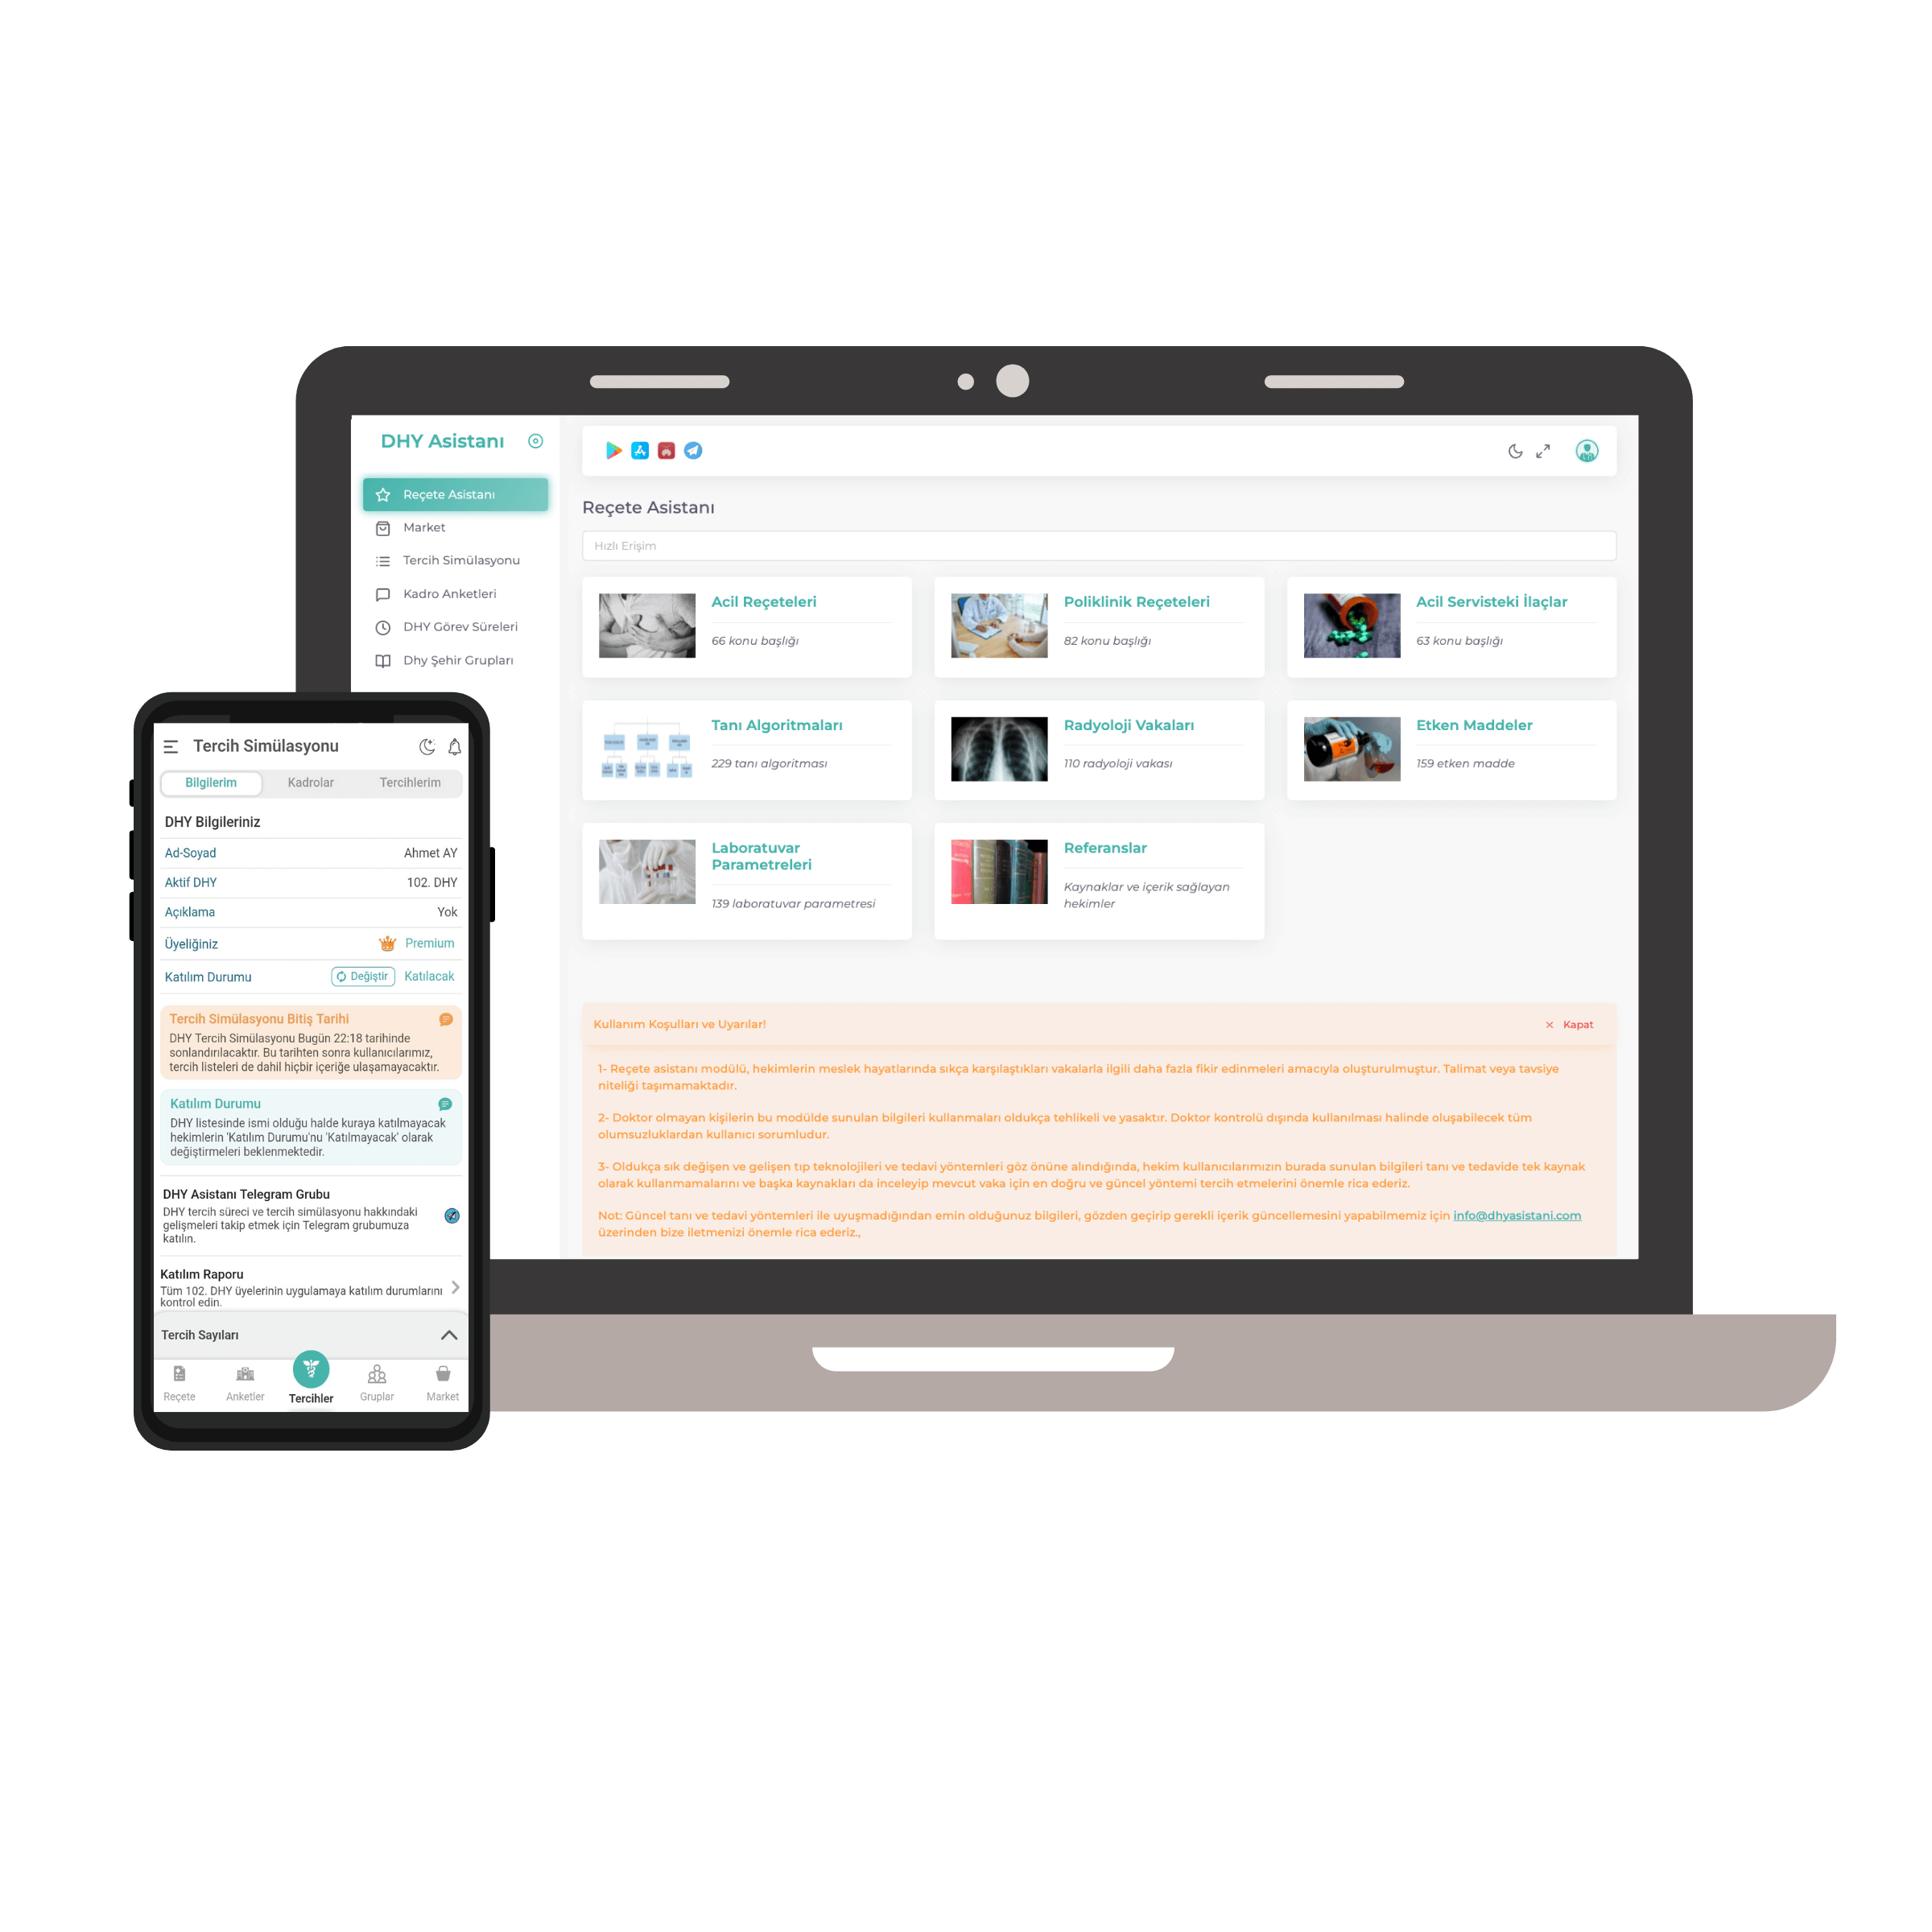

We've combined all your needs for exam preparation in the Plexia app.

The ideal way to study consciously and systematically during your preparation journey.

Complete coverage of all topics in medical literature